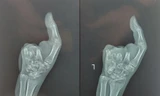

Tại Bệnh viện Nhi Đồng Thành Phố, bệnh nhi đã rơi vào tình trạng sốc chấn thương, sốc mất máu cấp. Qua thăm khám và kiểm tra hình ảnh, bác sĩ xác định cánh tay trái bệnh nhân dập nát gây đứt động mạch cánh tay.

Ê kíp phẫu thuật đã lấy ra nhiều đất cát từ vết thương, cắt lọc những vùng bị dập nát từ cánh tay xuống đến bàn tay trái đồng thời nối lại đoạn động mạch cánh tay (dài khoảng 15cm) đã bị đứt. Sau phẫu thuật, bệnh nhân vượt qua được nguy kịch, các chỉ số sinh hiệu dần ổn định.

BS Minh Tiến cho biết, sau gần 2 tháng điều trị mạch máu của bệnh nhi đã lưu thông tốt, tưới máu đầu chi hồng hào. Trẻ được ghép da và phục hồi dần tay trái. Đến nay, cánh tay có thể cử động giơ lên, hạ xuống như bình thường.